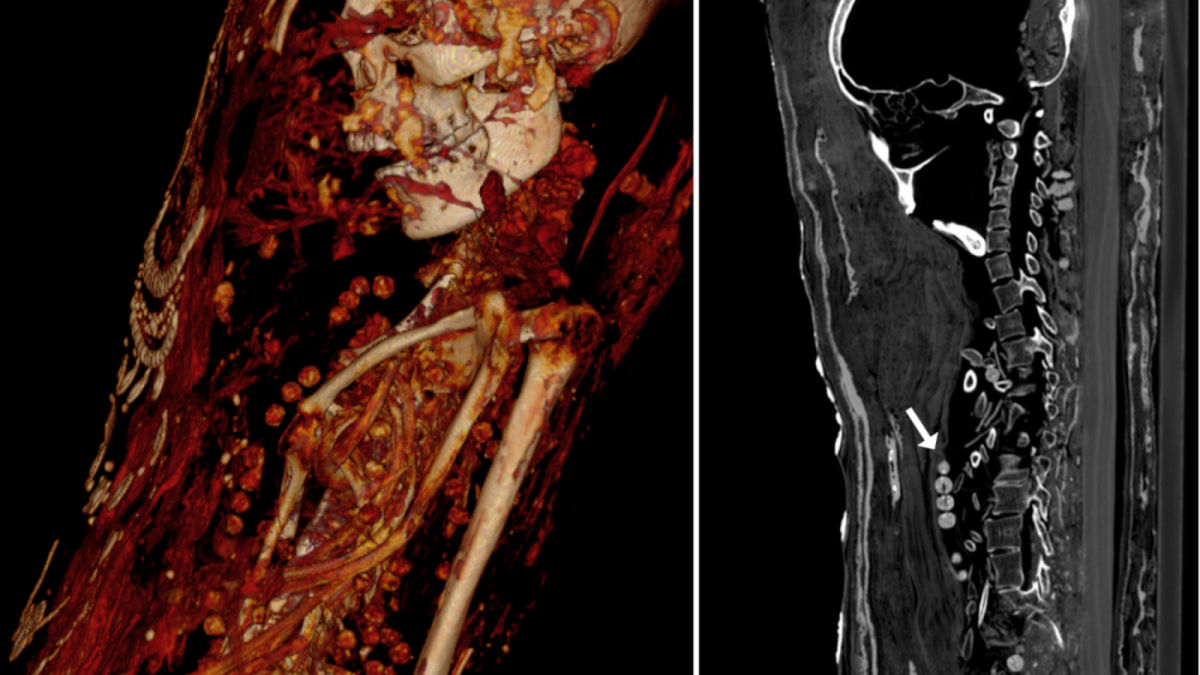

One of the difficulties of using mummies to learn about these things is that they can be challenging to wrap back up after pulling back the bandages. Luckily for us, modern technology has made doing that obsolete. Recently, a team of researchers created CT scan images of three mummies and published their findings.

The CT scan shows that the man was between 25 and 30 years of age when he died and that he had several cavities and unerupted teeth. He was only 164 cm tall (around 5’4″). Several of his bones are broken, though this is believed to be the result of careless handling by whoever discovered the remains.

Most curiously, there is no evidence that his brain was removed during the mummification process, as was standard in other cases. It also seems that few embalming chemicals were used to preserve him. This suggests that he was just wrapped, painted, and buried and that dehydration is what kept his corpse so well preserved.

The woman was between 30 and 40 years old and stood at 151 cm (4’9″). She shows signs of arthritis in her knees. Like many other Egyptians, she was buried in fine jewelry. Several necklaces appeared on the scan, suggesting she was well off. For reasons unknown, nails were also found in her abdomen. Like her male counterpart, her brain was not removed during mummification, either.

The last mummy was that of a girl in her late teens. She showed signs of having a benign tumor on her back, and all of her internal organs were still intact. Her coffin contains hairpins, suggesting that she wore her hair up as depicted in her portrait.